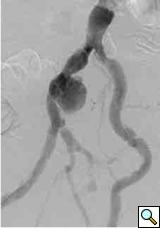

- Isolated iliac artery aneurysms are rare (Figure 2). Isolated internal iliac artery aneurysms are embolized. Pre-procedural embolization of internal iliac artery may also be necessary to prevents retrograde filling of the aneurysmal sac and late rupture. In case of aneurysm of distal part of external iliac artery contralateral access is gained and followed by a cross-over technique. This is done because the femoral access site will either be too close or may itself be part of the aneurysm. Same access applies for sub-intimal dissections and iliac occlusive disease in distal part of the external iliac artery. Majority of iliac aneurysms are accompanied with infra-renal aortic aneurysms that need to be treated concomitantly. Similarly, common iliac artery and proximal external iliac without proximal neck necessitates stent graft placement in the aortic bifurcation (Figure 3).